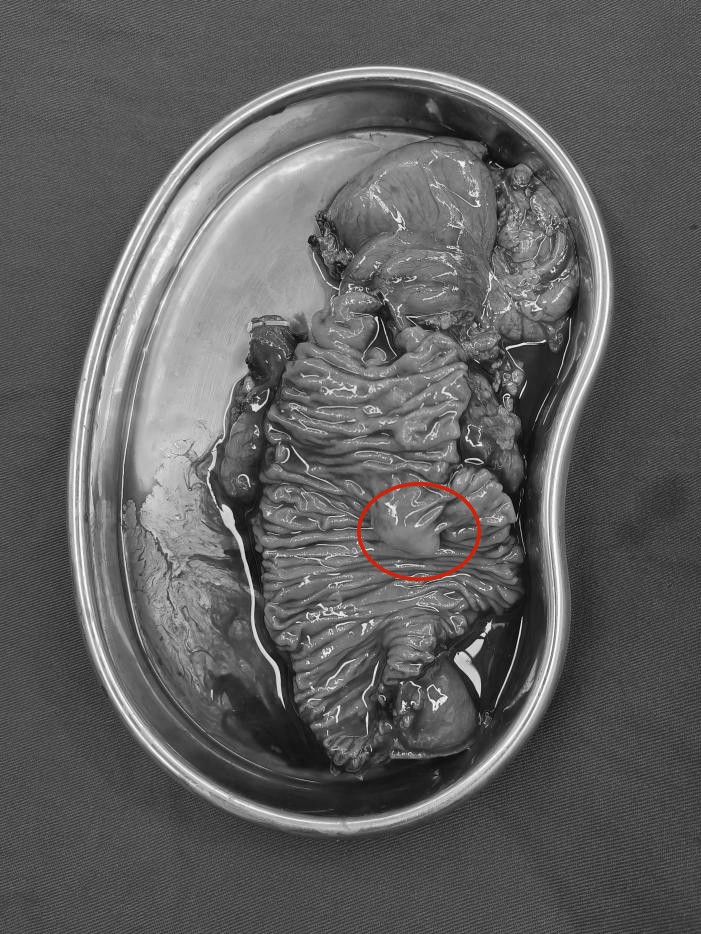

▶ 腹部增强CT、增强磁共振+MRCP均提示十二指肠壶腹部结节灶占位,考虑壶腹部周围癌,伴肝内外胆管、胰管、胆囊扩张。

A:十二指肠壶腹部结节状占位(红色箭头);

B:扩张的胆囊、胆总管、胰管(红色箭头)增强CT提示十二指肠壶腹部结节状占位:考虑壶腹部癌可能并肝内外胆管、胰管扩张。